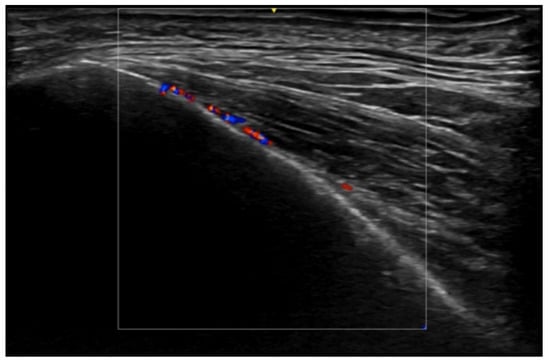

- Cataldo-Cerda, K.; Wortsman, X. Dissecting Cellulitis of the Scalp Early Diagnosed by Color Doppler Ultrasound. Int. J. Trichology 2017, 9, 147–148. [Google Scholar] [CrossRef]